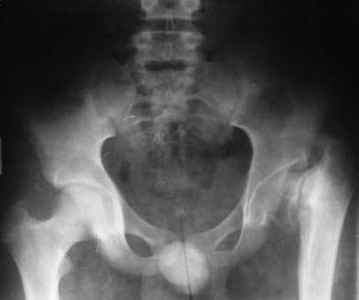

Больному 16 лет, болеет с рождения.Оперирован в детстве( корригируюшая межвертельная остеотомия с фиксацией пластиной), три года назад удалии пластину. Обратился к нам, выраженно хромота, укорочение бедра на 4 см, ходит безболезненно, отведение ограниченно при отведении и ротации. Буду рад вашим предложениям. С уважением Шухрат!

То, что Вы показали это не дисплазия, это врожденная COXA VARA.

Лечение в такой ситуации - VALGUS OSTEOTOMY, и, вероятно надо добавить дистальную транспозицию большого вертела. Укорочение бедра я советую поправить позже, после восстановления тазобедренного сустава.

Проблема не только в малом ШДУ, необходимо изменить наклон опорной площадки вертлужной впадины. Деваризирующая межвертельная остеотомия без полной коррекции (менее 130 градусов)+ периацетабулярная остеотомия. Без второго этапа перегрузка верхнелатерального отдела сохранит условия для этой формы артроза.

1.D-s: Coxa vara, colly lysis,(дистрофическая Coxa vara)

2. Рентгенография левого тазобедренного сустава в положении максимального приведения бедра: если головка занимает позицию 130 градусной инклиниции (имитация положения головки при нормализации ШДУ) то, или межвертельная по Пауелсу (проще), или подвертельная с латерализацией дистального фрагмента (для относительного удлинения шейки) (подвертельная без латерализации усилит имеющийся вальгус в колене)

Если 130 градусная иклинация невозможна (нет 60 градусов приведения) тогда операция SUPER (standart utilitarian procedure extremity reconstruction) hip по Droor Paley.

3. Выполнение периацетабулярной остеотомии дискутабельное: соотношение головка-впадина несферическая инконгруентность, хотя возможно через 3-6 месяцев вторым этапом с osteochondroplasty. Одномоментно невозможно из-за большого давления головки на впадину.